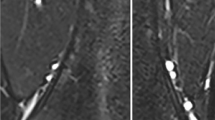

Each bone was scanned on two scanners, 1.5 T (Aera; Siemens Healthcare, Erlangen, Germany) and 3.0 T (Skyra; Siemens). We obtained a T1-weighted non-fat-suppressed sequence for each body part for anatomical localization. Multi-point Dixon volumetric interpolated breath-hold examination (VIBE) sequence was then performed using the following parameters: field of view (FOV)=200 × 100 mm2; repetition time (TR)=120 ms; echo time (TE)=2.3–13.8 ms with ΔTE=2.3 ms on 1.5 T, and TE=1.2–6.9 ms with ΔTE=1.2 ms on 3.0 T, with each TE corresponding to consecutive in-phase and out-of-phase TE; matrix = 192 × 96; slice thickness = 4 mm; number of slices = 3; flip angle 10° [9, 10]. The scanner console displayed inline images of water signal and fat signal, and parametric maps of fat percentage and R2*, allowing for region-of-interest (ROI) analysis. ROIs were hand-drawn by one observer (J.D.S.) on the fat percentage map for each specific bone (Fig. 1). In a long bone, because the epiphyses, diaphyses and metaphyses are known to have different proportions of yellow and red marrow [1], additional ROIs were placed at these locations. The ROI was drawn to capture the entire region, such as the entire metaphysis (Fig. 1). Three ROIs at consecutive slices were drawn for each area and the average fat fraction was recorded. For example, in a given long bone, the epiphyses (×2), metaphyses (×2) and diaphysis were sampled, producing 5 data points for each long bone. A cervical vertebra, lumbar vertebra, sacral vertebra and bilateral posterior iliac crests were also sampled. There were a total of 38 data points from a total of 14 bone sections. This method was duplicated for the 3-T scan using the same piglet bones. The techniques for 1.5 T and 3.0 T were identical.

In 14 piglet bones, we obtained 38 MRI-FF values at both 1.5 T and 3.0 T. Figure 1 is a representative image, displaying the piglet femur at 1.5 T. This figure demonstrates the methodology of selecting the region of interest — in this example the proximal and distal metaphysis — for MRI-FF calculation. The bones analyzed included bilateral tibiae (n=2), bilateral femora (n=2), bilateral humeri (n=2), cervical spine vertebrae (n=3), lumbar/sacral spine vertebrae (n=3) and bilateral iliac bones (n=2). Within each long bone, as expected, there were different degrees of cellularity in the epiphyses, metaphyses and diaphysis (MRI-FF 35.9±7.2%, 18.5±3.2%, 47.8±11.5%, respectively). With regard to cellularity in different body regions, we found the pelvis, spine and extremity of the piglet bone to have mean MRI-FF 15.5±7.2%, 24.8±3.1%, 31.3±13.4%, respectively.